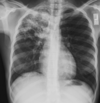

A

Consolidación alveolar

How well did you know this?

1

Not at all